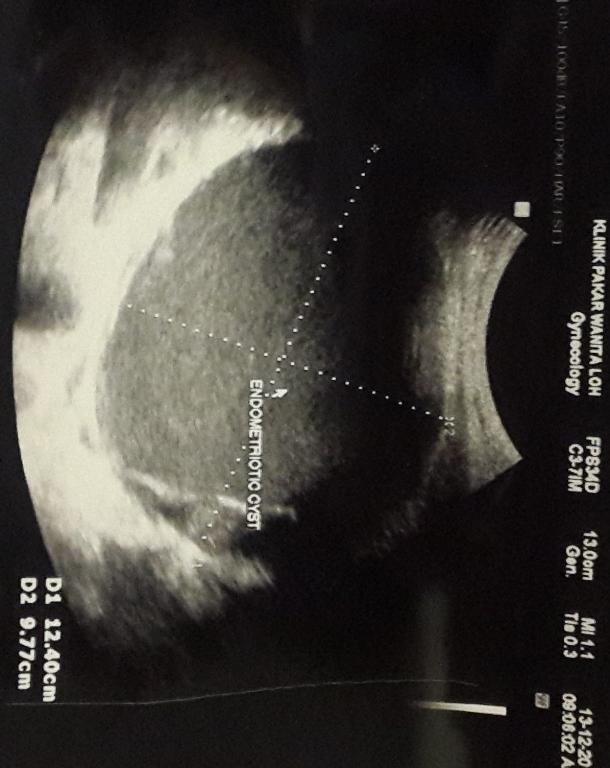

你好。。我之前照了B超。。发现卵巢有肿瘤。。。12cm。。我接下来应该怎样呢。。是需要手术切除吗? 我还不晓得是恶性还是良性。。医生开了norethisterone的药物给我。。让我月经来了后再给他看。。请问这样行吗。医生可以帮我看看。。B超里的肿瘤。。接近良性有多高呢?

您好,根据您的描述,卵巢囊肿较大,建议及时手术处理,避免出现蒂扭转等的情况。至于其性质,则在术后做病理后确诊。